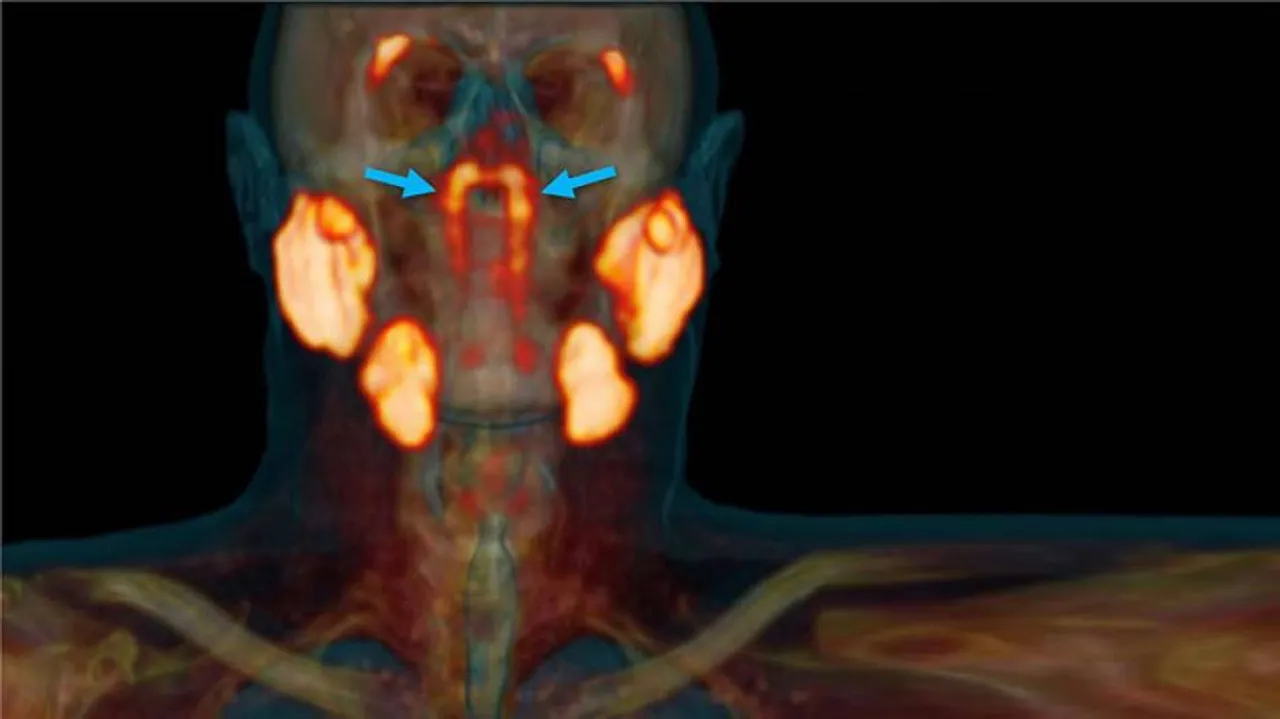

ନେଦରଲ୍ୟାଣ୍ଡର ବୈଜ୍ଞାନିକମାନେ ଏକ ନୂଆ କ୍ୟାନ୍ସର ସ୍କେନ୍ ଯାଞ୍ଚ କରୁଥିବା ବେଳେ ଗଳାରେ ଏକ ନୂଆ ଅଙ୍ଗ ବିଷୟରେ ଜାଣିବାକୁ ପାଇଥିଲେ। ଗବେଷଣାରୁ ଜଣାପଡ଼ିଲା ଯେ ମଣିଷ ଗଳାର ଉପରିଭାଗରେ ଗ୍ରନ୍ଥୀଗୁଡ଼ିକର ଏକ ଗ୍ରୁପ ରହିଛି। ବୈଜ୍ଞାନିକମାନେ ଏହି ଗ୍ରନ୍ଥୀର ନାମ Tubarial salivary glands ରଖିବା ସହିତ ଏହା ନାକର ଲୁବ୍ରିକେସନ୍ରେ ସାହାଯ୍ୟ କରିଥାଏ ବୋଲି ବୈଜ୍ଞାନିକମାନେ କହିଛନ୍ତି।

Radiotherapy and Oncology ଜର୍ନାଲରେ ପ୍ରକାଶିତ ଏକ ରିପୋର୍ଟ ଅନୁସାରେ, ରେଡିଏସନ୍ ଚିକିତ୍ସା ସମୟରେ ଯଦି ଏହି ଗ୍ରନ୍ଥୀଗୁଡ଼ିକ ଉପରେ କୌଣସି ପ୍ରଭାବ ନ ପଡ଼େ ତେବେ ଏହା ମଣିଷ ପାଇଁ ଉପକାରୀ ହେବ। ନେଦରଲ୍ୟାଣ୍ଡର ଏମ୍ସଟର୍ଡସର କ୍ୟାନ୍ସର ଇନଷ୍ଟିଚ୍ୟୁଟ୍ର ବୈଜ୍ଞାନିକ ପ୍ରୋଷ୍ଟେଟ୍ କ୍ୟାନ୍ସର ଯାଞ୍ଚ ପାଇଁ ପ୍ରସ୍ତୁତ କରାଯାଇଥିବା PSMA PET-CT ନାମକ ସ୍କାନ୍ର ପରୀକ୍ଷଣ କରୁଥିବା ସମୟରେ ରେଡିୟେକ୍ଟିଭଭ ଟ୍ରେସରକୁ ରୋଗୀର ସରିର ଇଞ୍ଜେକ୍ଟ କରାଯାଇଥିଲା ରେଡିୟେକ୍ଟିଭଭ ଟ୍ରେସର ପାଇଁ ମଣିଷ ଶରୀରେ ଥିବା ନୂଆ ଅଙ୍ଗ ବିଷୟରେ ଜଣାପଡ଼ିଥିଲା।/odishatv-khabar/media/post_attachments/aajtak/images/photo_gallery/202010/new-organ_020212.jpg)

ଗଳାର ଉପରିଭାଗରେ ଥିବା ଏହି ଗ୍ରନ୍ଥୀଗୁଡ଼ିକର ଲମ୍ବ ୧.୫ ଇଞ୍ଚ ରହିଛି। ଏହି ନୂତନ ଗ୍ରନ୍ଥୀଗୁଡ଼ିକ salivary glands ଭଳି। ୧୦୦ ଲୋକଙ୍କ ଉପରେ ହୋଇଥିବା ରିସର୍ଚ ସମୟରେ ପ୍ରାୟ ୧୦୦ ଲୋକଙ୍କଠାରେ ହିଁ ଏହି ଗ୍ରନ୍ଥୀ ଥିବା ଜଣାପଡ଼ିଥିଲା।